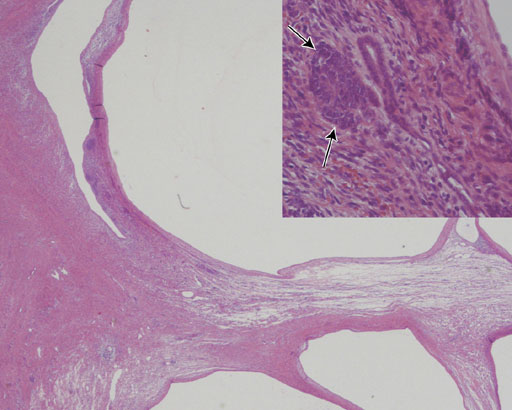

• 図8 病理組織像

Multilocular cystic renal tumorはまれな嚢胞性腎腫瘍である.3ヶ月から2歳までの男児に多く,残り1/3は50―60歳代の女性に認める.小児例では無症状のことが多い.病理学的には良性であるcystic nephromaと悪性ポテンシャルを有するCystic partially differentiated nephroblastoma(CPDN)とに分類される.出血,壊死はなく石灰化を認めることはまれである.嚢胞間の交通はなく扁平な一層の上皮に覆われる.CPDNは間質内に分化した尿細管やblastemal element, embryonal elementを有し,再発,転移の報告例がある.画像所見からこの二者は鑑別困難とされる.外科切除で最終診断がされる.画像上で鑑別すべき疾患は,出血,壊死をきたし嚢胞変性となったWilms tumor,clear cell sarcoma, cystic variations of mesoblastic nephroma, renal cell carcinoma, multicystic dysplastic kidney(segmental form)である.本症例はMR画像から出血,壊死の所見はなく,CT所見からも石灰化は認めず,Multilocular cystic renal tumorとの診断は比較的容易と思われる.